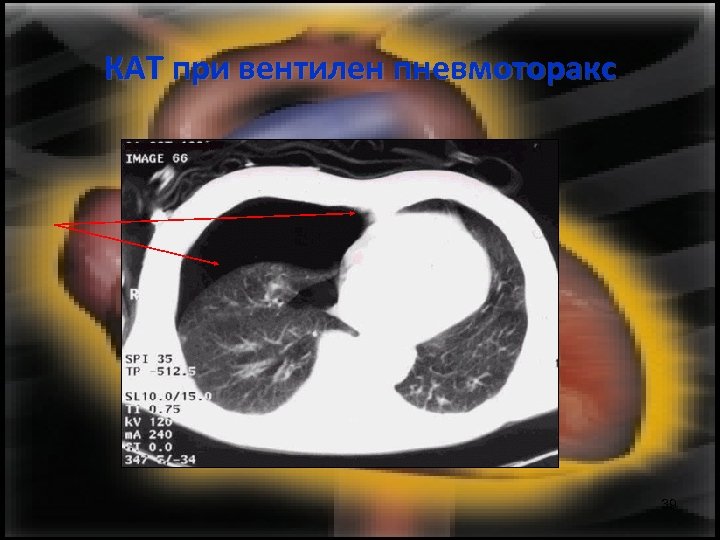

КАТ при вентилен пневмоторакс 39